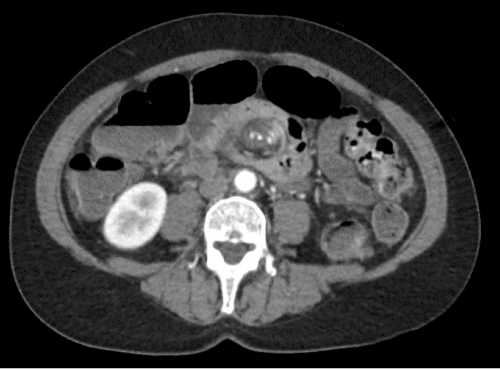

Figure 1. Axial Cut of Abdominal CT Showing Whirlpool Sign. Published with Permission

The patient is a 55-year-old female with rheumatoid arthritis, hypertension, and hemorrhoids who presented to our institution in 2020 with three days of constipation and abdominal pain. She reported that she attempted to use an unknown laxative and enemas to no avail. The patient denied nausea or vomiting. On presentation, she was afebrile and hemodynamically stable. Laboratory workup was unremarkable, with no leukocytosis and normal lactate. She was given lactulose in the emergency department, had a large bowel movement, passed gas, and reported feeling better. An abdominal CT was performed, demonstrating a midgut "whirlpool sign."

Small bowel volvulus is an uncommon cause of small bowel obstruction in adults. Only 1.7-6.2% of small bowel obstruction cases in adults are caused by volvulus. Classically, volvulus is a pediatric surgical disease secondary to congenital malrotation. Our patient did not present with typical findings of small bowel obstruction. She did not have nausea or vomiting, and her constipation resolved following the administration of lactulose in the emergency department. Of note, the CT scan performed at the initial presentation revealed a "whirlpool sign," a radiographic finding associated with (but not specific to) small bowel volvulus. The whirlpool sign is also associated with closed-loop small bowel obstruction or, very rarely, enteritis. It is described as the clockwise rotation of the superior mesenteric vein and small bowel mesentery around the superior mesenteric artery.5 In one review in an oncologic population, the association between the whirlpool sign and small bowel volvulus was assessed.6 It was identified in 33 of 1493 patients evaluated for small bowel obstruction secondary to volvulus, and 11 were identified on surgery to have a volvulus. The lesson is that while a whirlpool sign suggests a small bowel volvulus, it is not diagnostic. For this reason, we initially chose to observe and serially examine the patient.